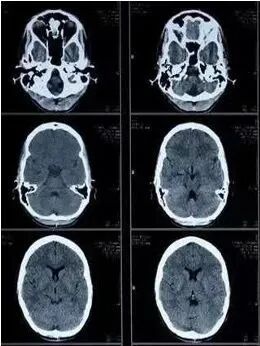

二、CT在临床上也称为电子计算机断层扫描,CT实质上与DR很相似,都是X线检查的分支之一,密度上的概念依然适用。CT对人体部位进行断层扫描,就好像把体检者横向 “切分”成了统一厚度、统一间距的“片”,经过放射线穿透,留下一幅幅相似又不同的影像。这些断层影像通过计算机进行三维重建,医生读片时就能立体把握体检人的情况了。与DR相比,CT扫描出来的是断层图像,器官之间无重叠且显示清晰,密度分辨率更高。所以,CT可以更好地显示由软组织构成的器官,例如脑、脊髓、肺、胆、纵膈以及盆部器官等,并可以在良好的解剖图像背景上显示出病变的影像。

CT检查适用于头部、胸部、腹部、盆腔、脊柱、四肢、骨骼等处,CT诊断由于它的特殊诊断价值,已经广泛应用于临床,特别是在肿瘤的诊断上更是具有很高的应用价值。但由于CT设备较为昂贵,检查费用也会偏高,对于某些部位的检查和诊断价值,尤其是定性诊断,还有一定限度,所以在临床上并没有将CT检查视为常规诊断手段。应在了解其优势的基础上,合理选择应用,此外,CT诊断辐射量大于DR,所以怀孕或备孕期女性不宜进行CT检查。